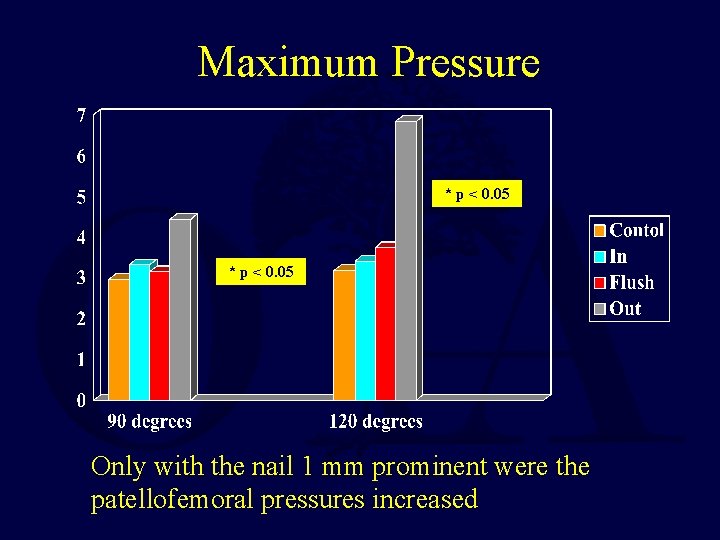

Mean Contact Area

Maximum Pressure * p < 0. 05 Only with the nail 1 mm prominent were the patellofemoral pressures increased

Retrograde Femoral Nailing • A cadaveric study using Fuji film demonstrated NO deleterious effects on the patello-femoral joint with a properly inserted retrograde IM nail • The orthopaedic literature does NOT support decreased knee motion or increase knee pain with a retrograde nail